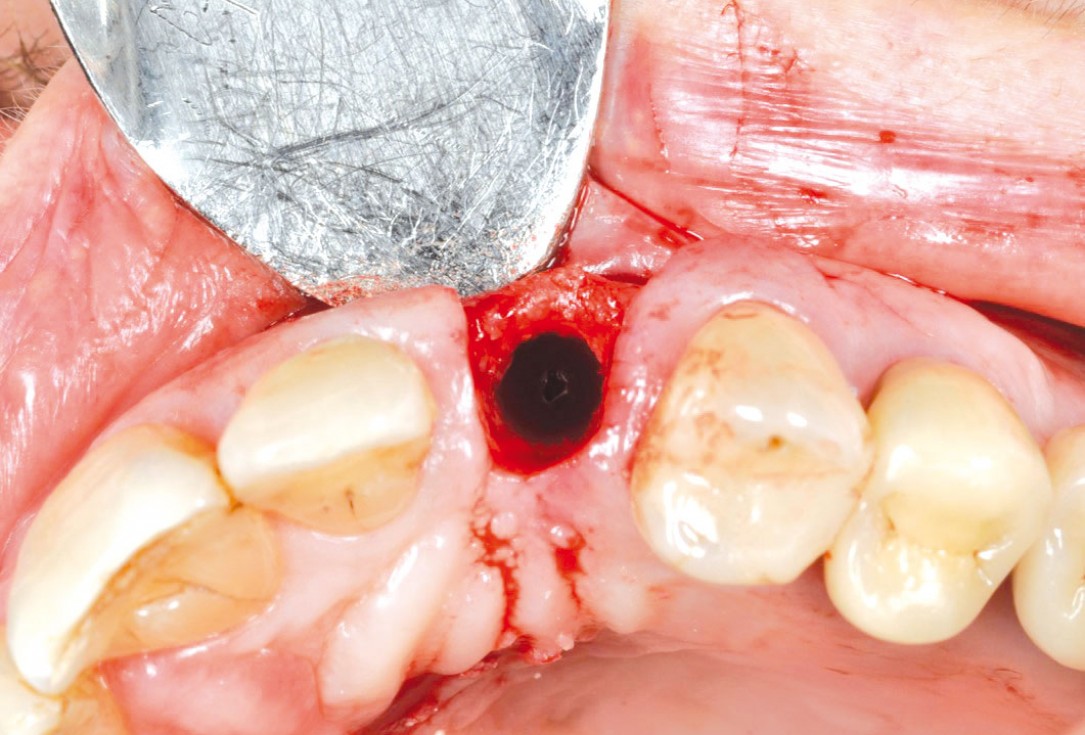

botiss cerabone® & collagen fleece for immediate implantation - Clinical case by Dr. D. Jelušić

Clinical situation before extraction and implantation